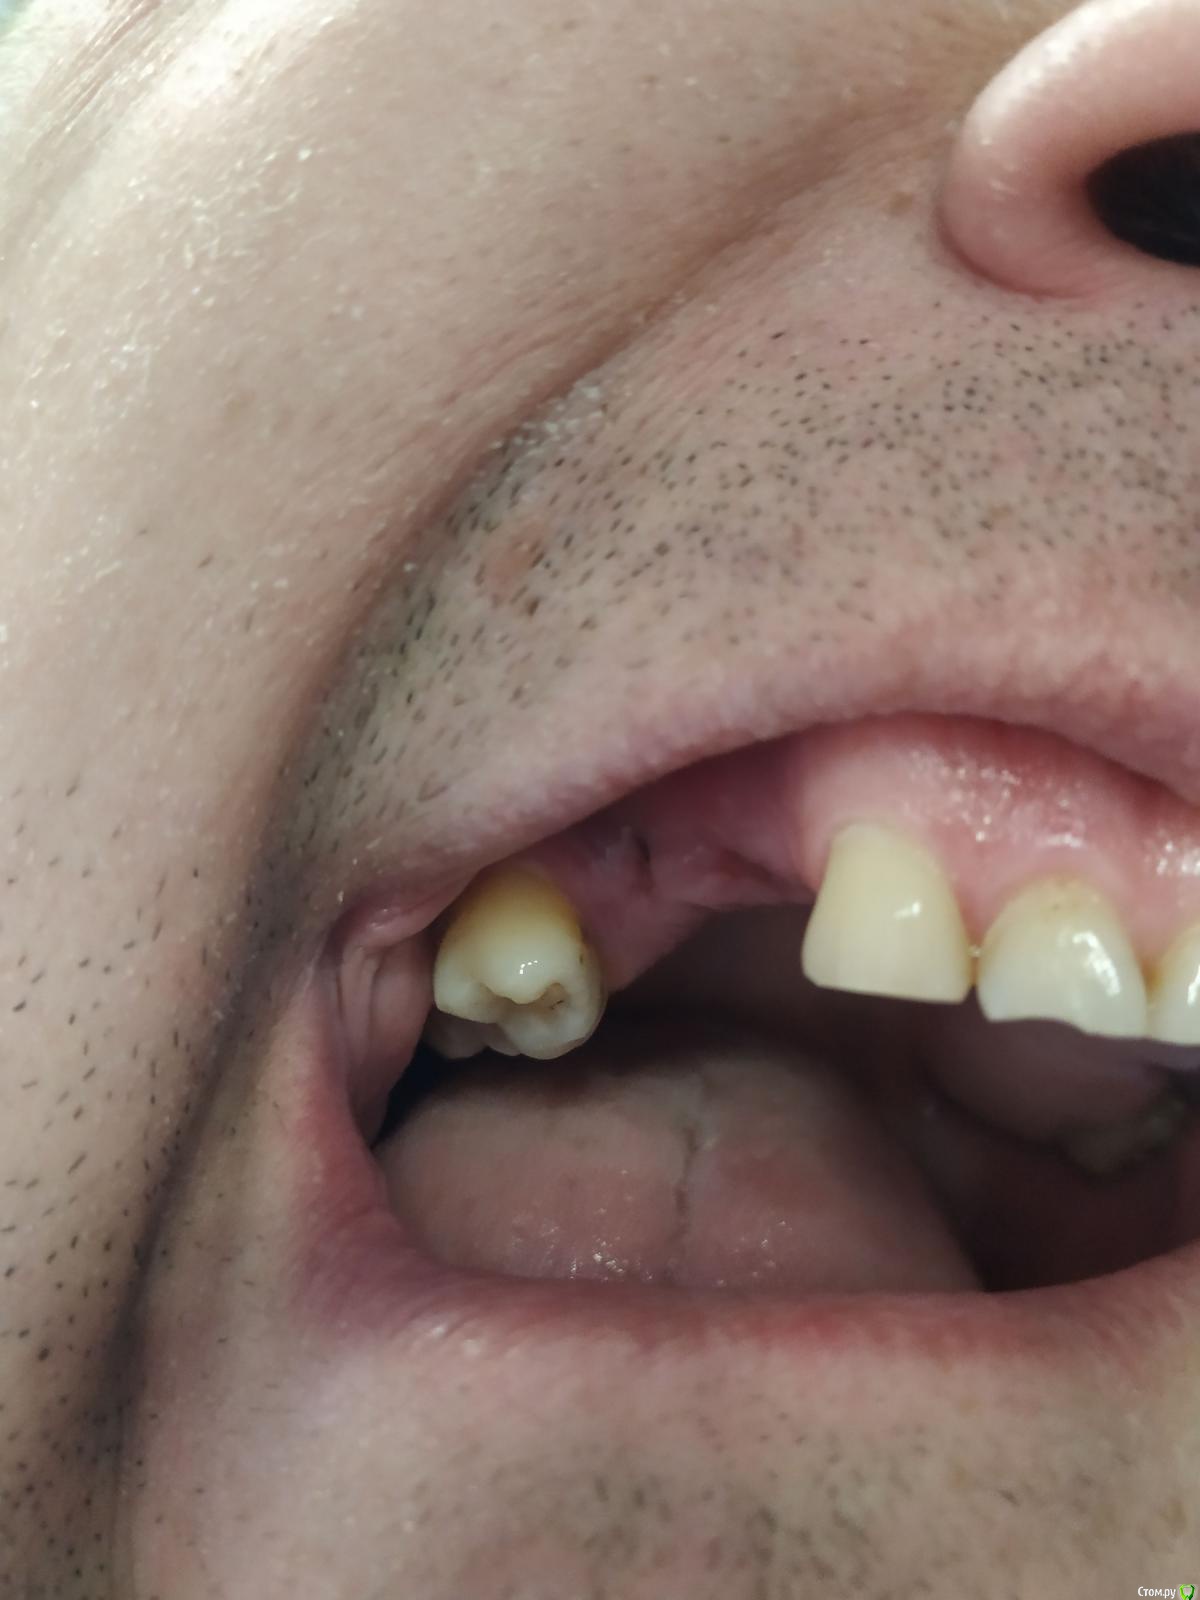

Владимир Серпухов Опубликовано 18 апреля, 2019 Автор Поделиться Опубликовано 18 апреля, 2019 Во, чет глистовое полезло Ссылка на комментарий